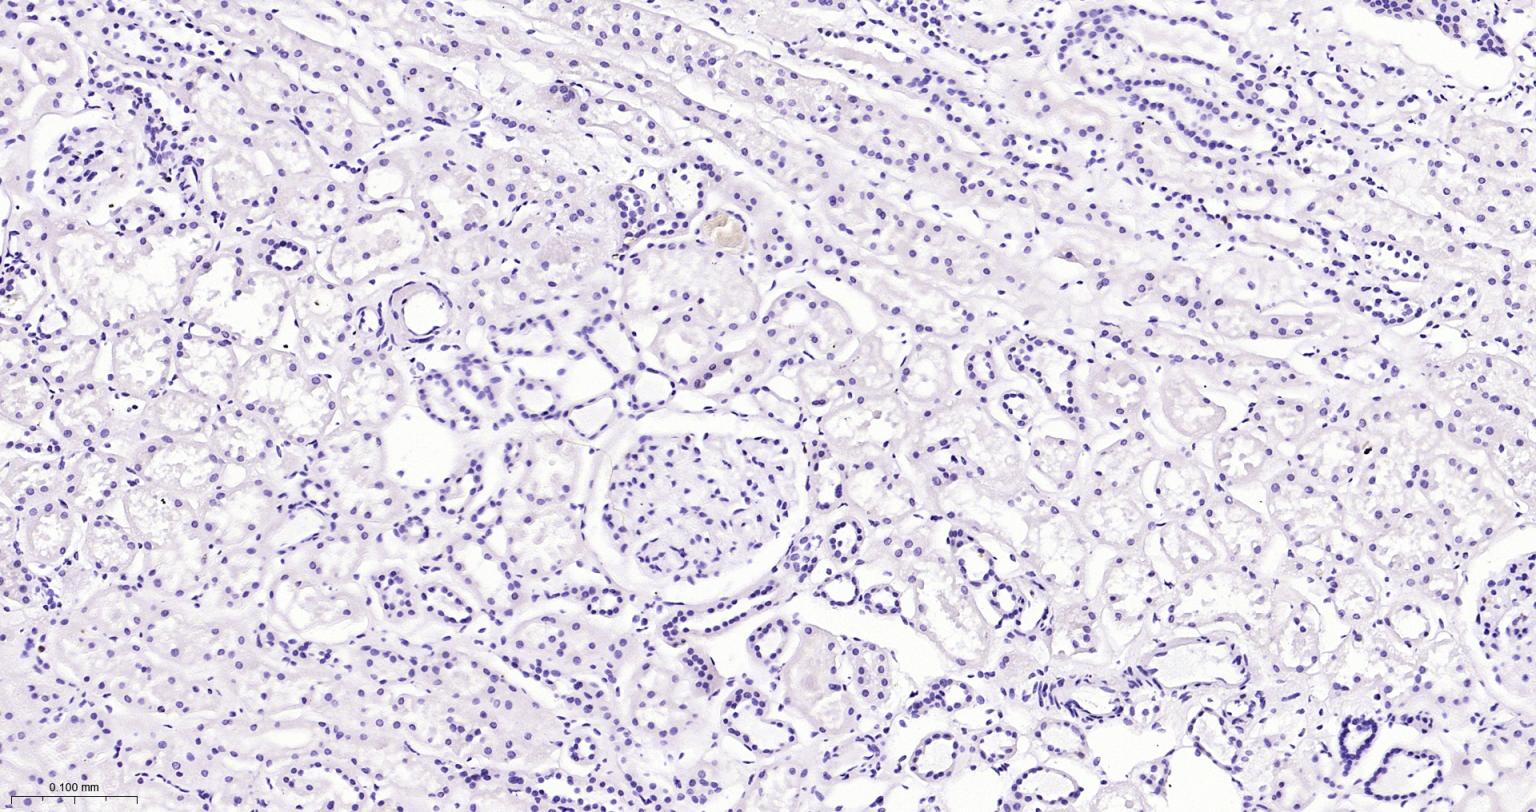

(Negative control)Paraformaldehyde-fixed, paraffin embedded Human Kidney; Antigen retrieval by boiling in sodium citrate buffer (pH6.0) for 15 min; Antibody incubation with CD45 Monoclonal Antibody, Unconjugated(bsm-54757R) at 1:200 overnight at 4°C, followed by conjugation to the bs-0295G-HRP and DAB (C-0010) staining.